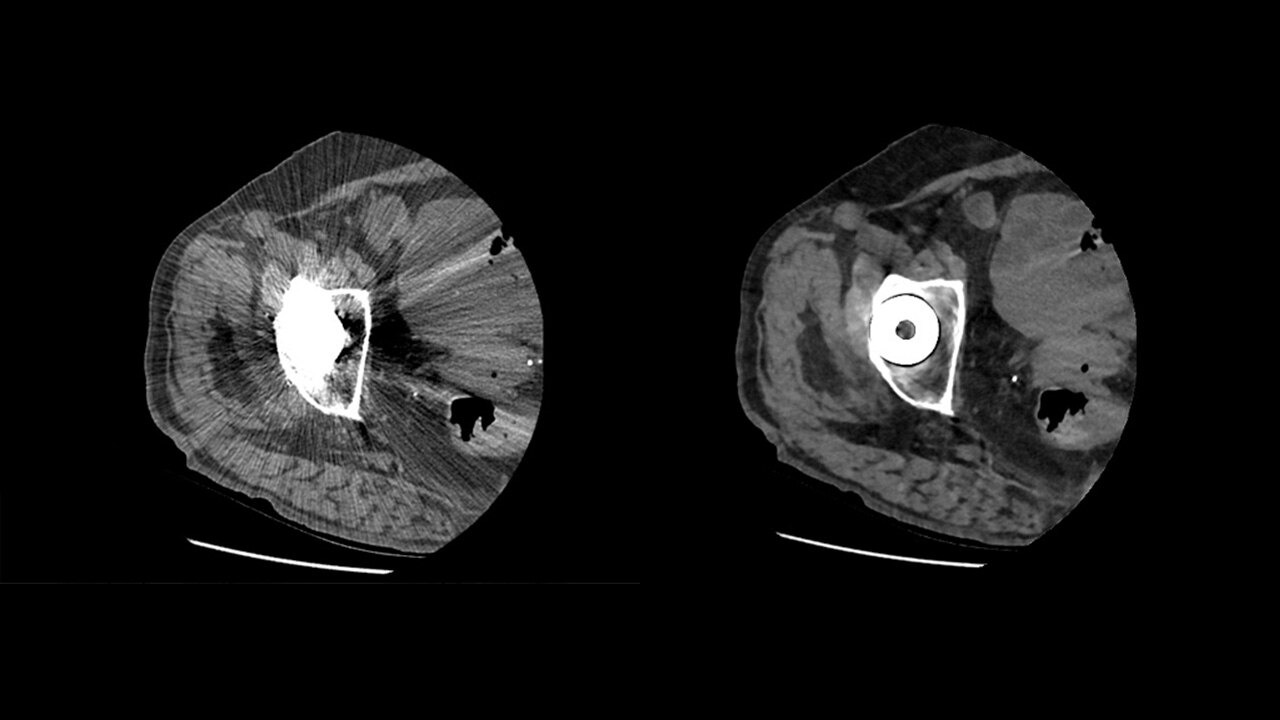

ΑΞΟΝΙΚΟΣ ΤΟΜΟΓΡΑΦΟΣ

Ο υπερσύγχρονος αξονικός τομογράφος Revolution Maxima του αμερικανικού οίκου General Electric Healthcare, με ανιχνευτή 128 τομών αποτελεί ένα σημαντικό άλμα προόδου στη διαγνωστική απεικόνιση και πλέον είναι διαθέσιμος στην κλινική μας. Ο Revolution Maxima της GE ανταποκρίνεται σε ένα ευρύ φάσμα κλινικών εφαρμογών, από την επείγουσα ιατρική και την ογκολογία έως τις προληπτικές εξετάσεις ρουτίνας.

- Αξονική αγγειογραφία

Απεικόνιση εξαιρετικής ποιότητας

Ανιχνευτές προηγμένης τεχνολογίας που δημιουργούν εξαιρετικά λεπτές

τομές, με πολύ υψηλή χωρική ανάλυση.